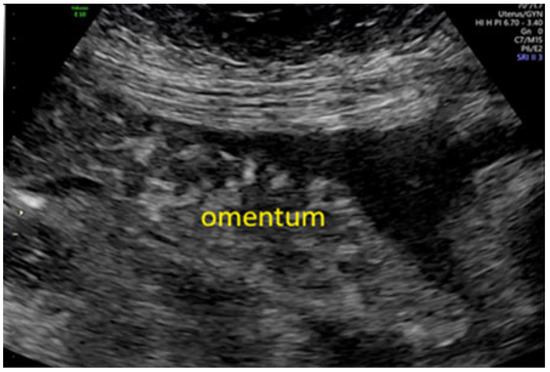

Background: Ovarian cancer is one of the most lethal gynecological malignancies, often diagnosed at an advanced stage. The prognosis is generally poor, with high recurrence rates and limited long-term survival. Understanding the genetic and molecular...